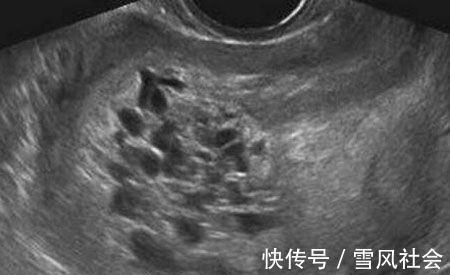

河南驻马店关某5个月前被查出怀孕,虽然是满心欢喜但是她却嫌做产检麻烦,除了确诊怀孕那天到过医院,其余时间5个月内再无涉足入医院半步。直到某天她腹部突然剧痛难忍,家人把她紧急送院,做了彩超检查后众人大惊失色,医生说她的肚子里根本看不到宝宝,只能看到一些类似蝌蚪状的小生物。后来医生经过精细检查,才诊断出关某的情况为葡萄胎,因受精卵异常所致,出现类似“葡萄”“小蝌蚪”等形态的小细胞。

你听过的产子最高数量是多少个呢,5个?8个?或者是一支足球队的人数?其实在我国古代曾有妇女产子六百的记录,后来人们才发现这数据不真实,不是数量上含水分,而是生出的这些怪胎全部是因为妊娠后胎盘绒毛滋养细胞增生、间质水肿因而导致出现大小不同的水泡,他们被称为是“奇胎”或“水泡状胎块”,因看上去像一串串葡萄,现医学名称其为“葡萄胎”。2、葡萄胎分类随着科学家对其研究深入,葡萄胎现被分为两类:(一)完全性葡萄胎胎盘绒毛全部受累,整个宫腔充满水泡,弥漫性滋养细胞增生,无胎儿及胚胎组织可见;(二)部分性葡萄胎部分胎盘绒毛肿胀变性,局部滋养细胞增生,胚胎及胎儿组织可见,但胎儿多死亡,有时可见较孕龄小的活胎或畸胎,极少有足月婴诞生。